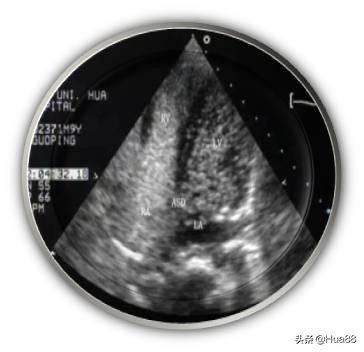

相关检查 医生如怀疑或排查患者是否存在卵圆孔未闭,通常会完善以下检查。由于超声心动图可以直观地显示房间隔解剖结构及心脏内血流分流情况,因此超声心动图是卵圆孔未闭的最 佳诊断检查。 临床上常用的超声心动图包括经胸超声心动图(TTE)、经食管超声心动图(TEE)和经颅多普勒超声声学 造影(cTCD)。 经胸超声心动图(TTE) 性价比高,操作简单、无痛苦,但该检查会受到肥胖和肺气过多等因素的干扰,检出率不高,且难以准确测 量未闭的卵圆孔大小,一般应用于儿童及部分成年人。 经胸超声心动图声学造影(cTTE)可以提高检出率,了解患者有无心脏内血液异常分流。操作时需要静脉注 射声学造影剂。 经食管超声心动图(TEE) 是诊断卵圆孔未闭的“金标准”和首选方法。该检查可以指导医生对卵圆孔未闭进行分类,从而指导治疗。 该检查属于半创伤性检查,操作过程中患者比较痛苦,类似于胃镜检查,插管会造成患者恶心、呕吐等不 适。检查前后患者须禁食、禁水。 经食管超声心动图声学造影(cTEE)亦可用于判断心脏内血液异常分流情况。 此外,三维经食管超声心动图(三维TEE)能够为二维TEE图像提供有力补充,帮助医生了解实时未闭卵圆 孔的状态,更有利于指导治疗。 经颅多普勒超声声学造影(cTCD) 简单、无创、安全。检查心脏内血液有无分流的一种常用方法,但是不能定性诊断卵圆孔未闭。作为卵圆孔 未闭筛查的一种方法,通常需要进一步进行经胸超声心动图(TTE)、经食管超声心动图(TEE)等检查作 为补充。 心导管检查、对比分析双源CT冠状动脉成像和心脏磁共振成像(MRI)可以发现卵圆孔未闭,但费用较高, 敏感性相对较差,临床较为少用。

右心声学造影+发泡实验